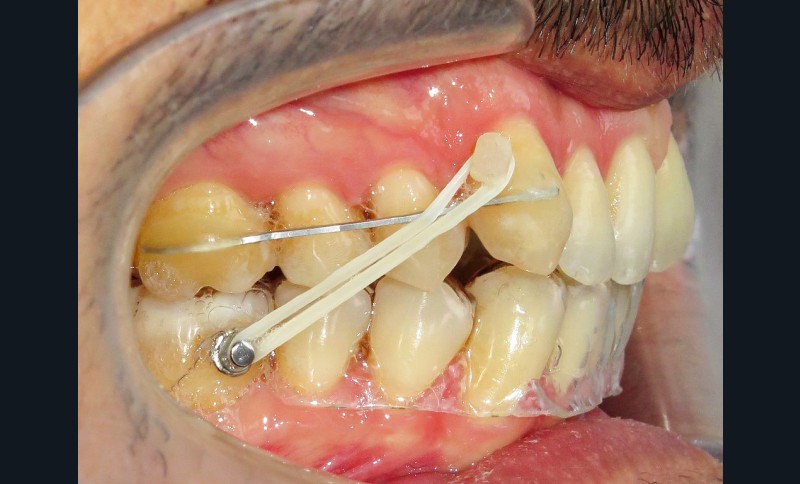

Dans un premier temps (fig. 2), la 28 (et la 18) a été extraite pour faciliter le déplacement de la 27 (DDM postérieure). Une minivis palatine a été placée entre 26 et 27 et des boutons ainsi qu’un sectionnel collés sur les faces vestibulaires des 26 et 27. Des chaînettes élastomériques ont été ancrées sur les boutons et la minivis, en passant au-dessous des faces occlusales de ces dents. Les chaînettes reliant un dispositif vestibulaire et un palatin et prenant appui sur les faces occlusales des molaires du secteur 2, les mouvements dentaires induits sont un déplacement vestibulo-palatin associé à une ingression des 26 et 27. Les minivis sont des ancrages absolus qui ne nécessitent pas d’utiliser l’ancrage des dents adjacentes ou antagonistes, ce qui préserve d’effets sur ces dernières.